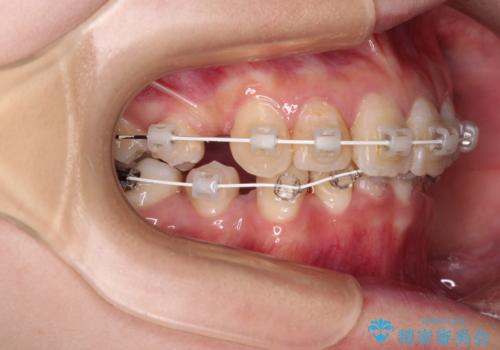

デコボコと深い咬み合わせ ワイヤー装置での抜歯矯正

- 矯正装置

- 審美装置

- 内側に倒れ込んだ歯や下の前歯が隠れてしまうほどの咬み合わせを改善したいとのことで来院された患者様です。

下顎の叢生を解消するために抜歯が必要であり、奥歯の咬み合わせや口元の印象から、上顎も同様に抜歯と判断し、上下左右の第1小臼歯4本抜歯してワイヤー装置にて矯正治療を行うこととしました。

咬み合わせが深く、そのままでは上顎の抜歯スペースが閉じきらない可能性があったため、治療初期から深い咬み合わせを改善させるように試みました。

実際にはなかなか改善されず、当初予定よりも治療期間がやや長期化してしまいました。